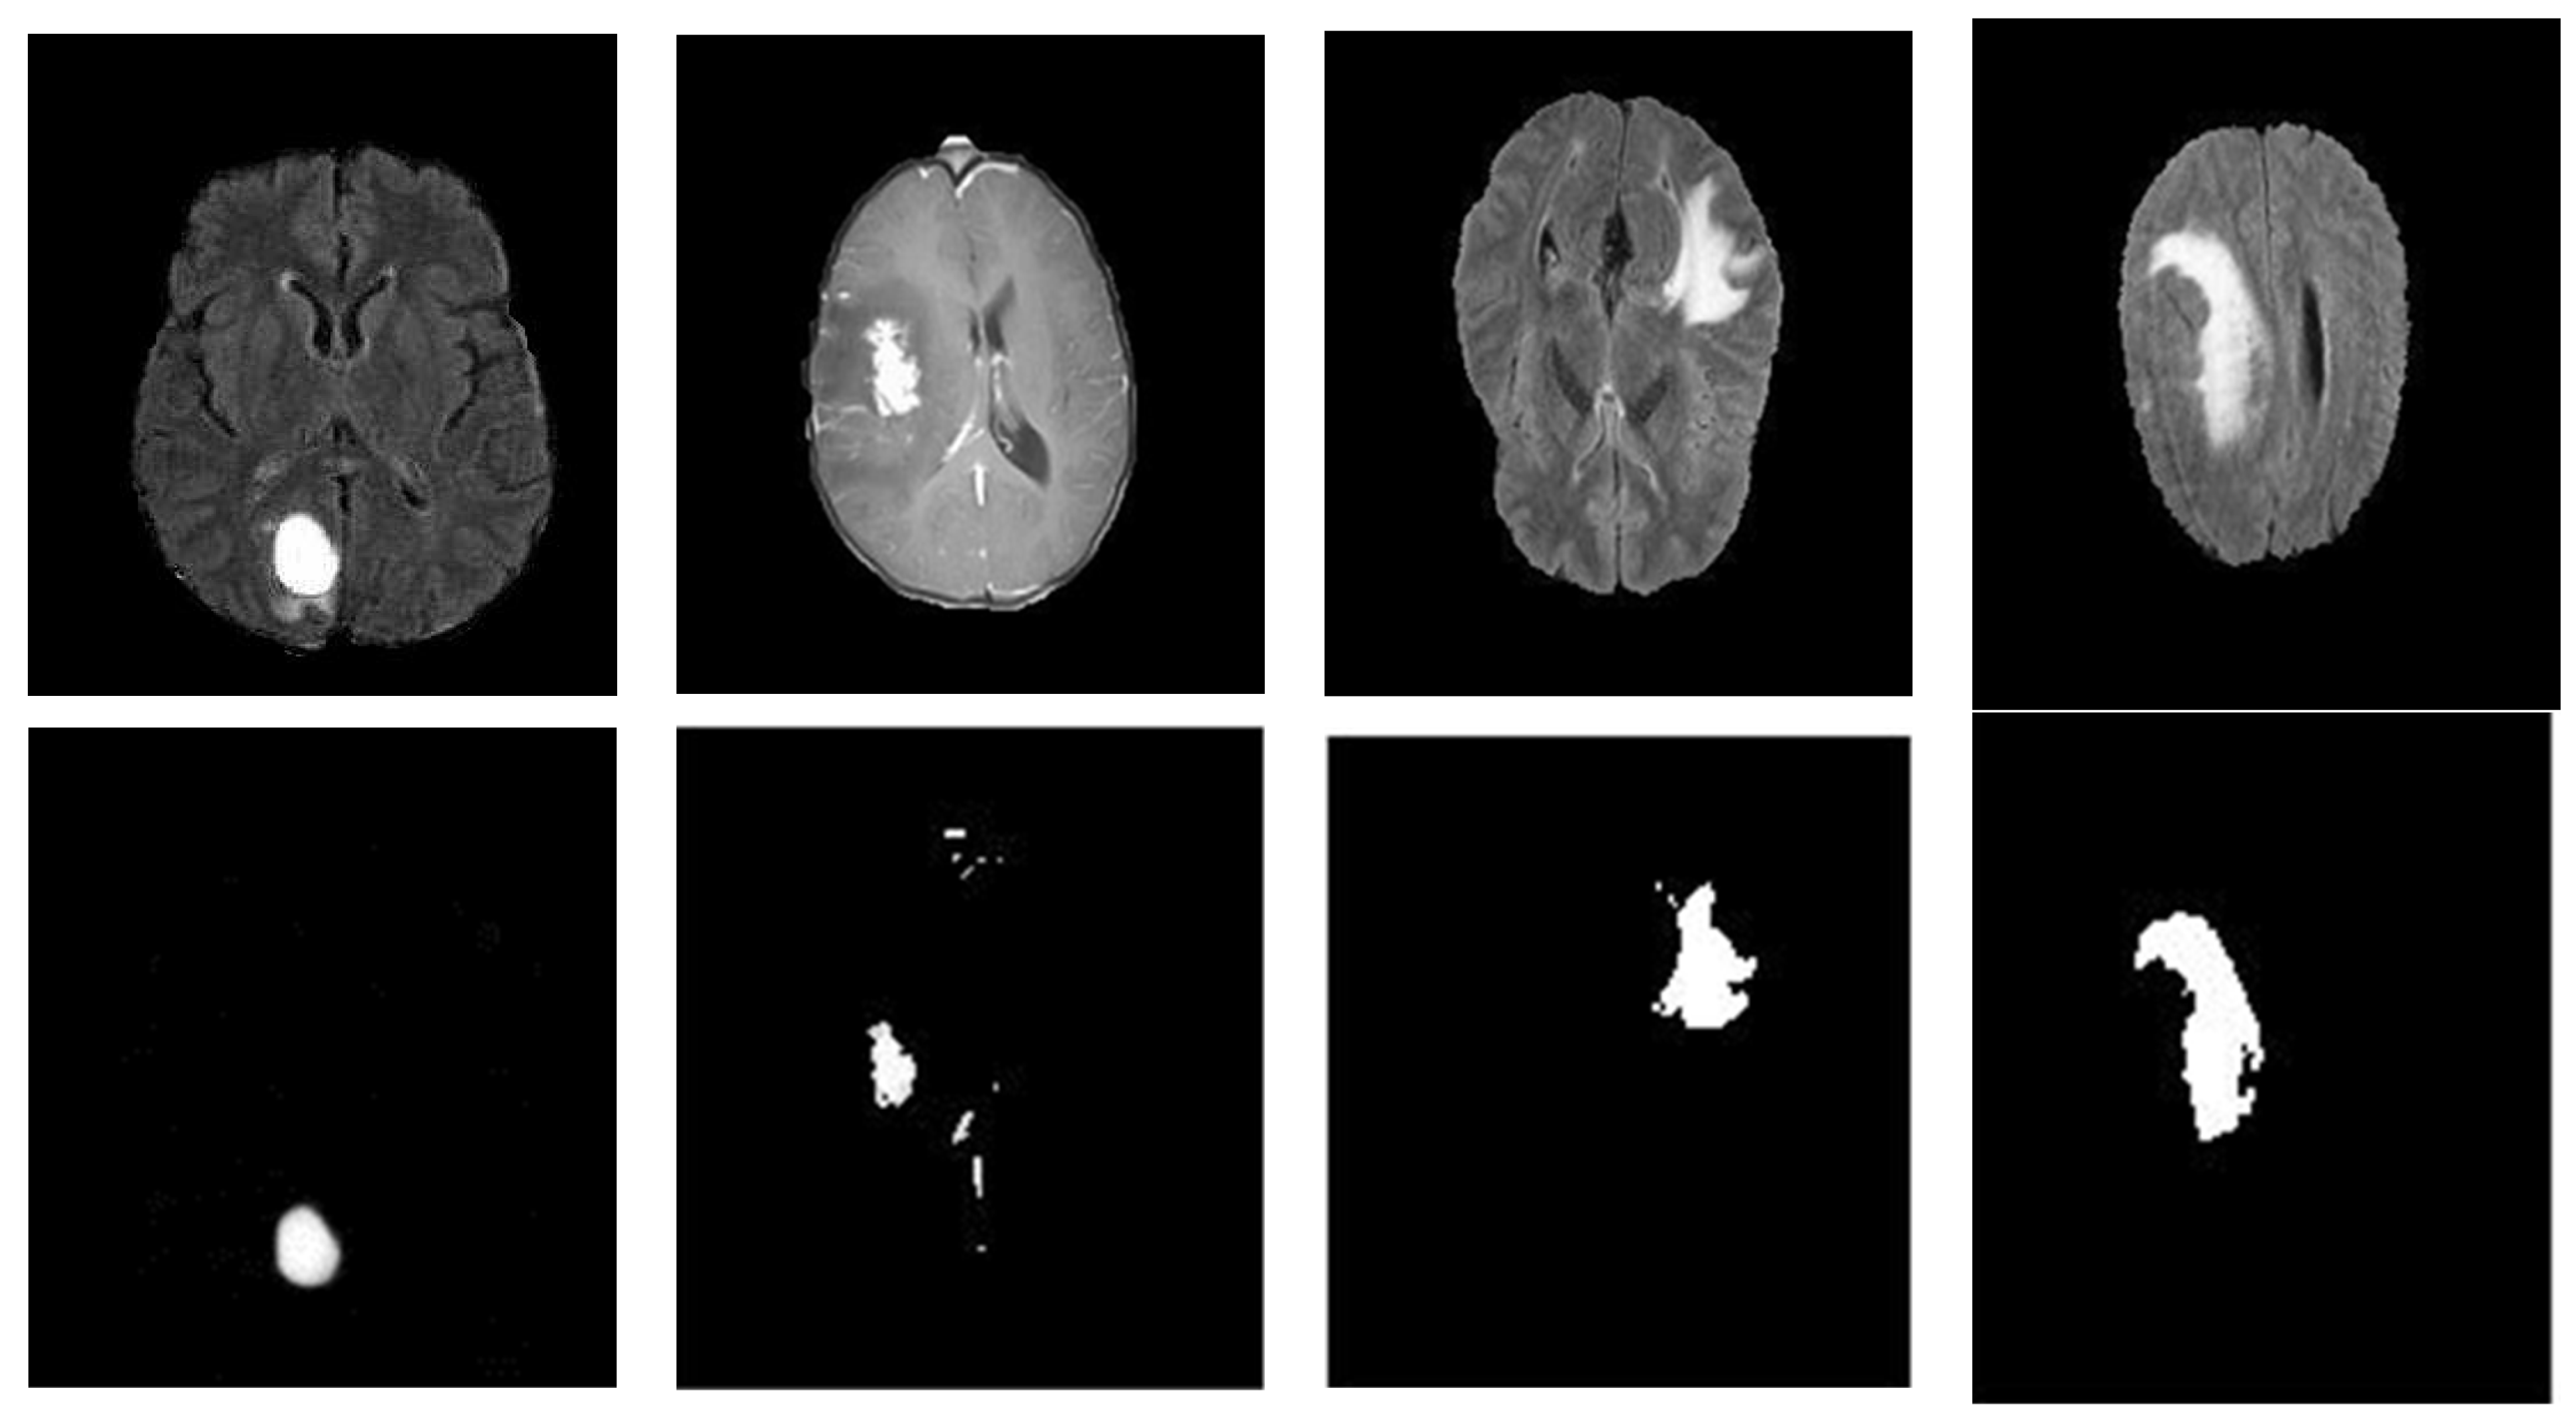

3.1. Image Pre-Processing

3.2. ROI Detection

3.3. Tumor Segmentation